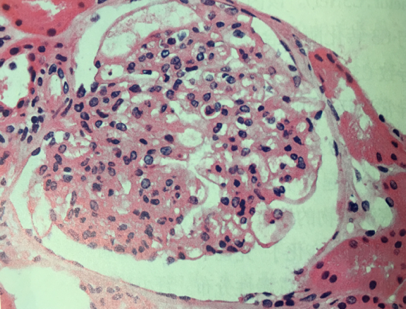

5.毛细血管内增生性肾小球肾炎(endocapillary proliferative glomeru-lonephritis)

毛细血管内增生性肾小球肾炎(endocapillary proliferative glomeru-lonephritis),多在扁桃体炎等上呼吸道感染1~2周后发病,其发病与感染,尤其是A组乙型溶血性链球菌感染有关,所以又叫感染后或链球菌感染后肾小球肾炎(post-infectious or post-streptococcal glomerulonephritis)。多见于儿童青少年。

(1) 病理变化

光镜下: 弥漫性肾小球肿胀,细胞数目显著增多(hypercellular)是其主要特征。系膜细胞、内皮细胞明显增生肿胀为主,早期尚可见多少不等的中性白细胞和单核细胞浸润。增生的细胞使毛细血管管腔狭窄、甚至闭塞,从而导致肾小球缺血。少数严重病例可见肾小球壁层和脏层上皮细胞增生, 壁层细胞的增生形成新月体,易引起肾小球纤维化,如数量少,对功能影响不大。如病变广泛可发展为新月体性肾炎。

间质充血、水肿,少量淋巴细胞和中性白细胞浸润。肾小管上皮细胞可有水变性、脂肪变性及玻璃样变等。管腔内常含有各种管型,如透明管型、红细胞管型、白细胞管型等。

免疫荧光: 可见免疫球蛋白IgG和补体C3呈粗颗粒状沉积于肾小球毛细血管壁。

电镜下: 除证实肾小球内增生的细胞主要是系膜细胞和内皮细胞,渗出的细胞是中性粒细胞等外,可见基底膜外侧或上皮下有高密度、大团块电子致密物沉积。沉积物从基底膜向外侧形成驼峰状突起(hump)。

(2) 临床表现 表现为急性肾炎综合征。多数预后较好。